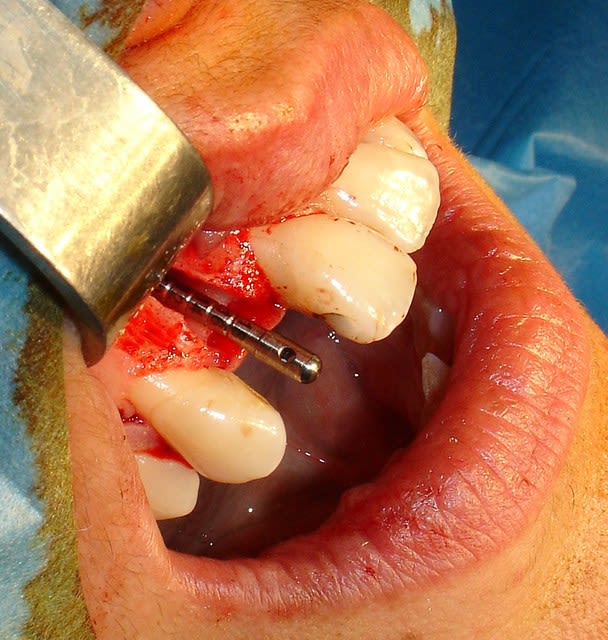

Tiens pour agrémenter! Cet Après midi une extraction implantation. Je n'ai pas oser la mise en charge immédiate si certains l'aurait fait lachez vous.

J'ai fait sauter la table vestibulaire exprès car je ne vois pas comment elle aurait pu etre vascularisée et à part me faire un séquestre osseux et des ennuis j'ai reconstruis.

Regardez les images;

Si certains n'auraient pas extrait argumentez pour traiter en palatin et la felure englobé par le granulome m^me si ce n'est pas mis en évidence sur le scan.

En plus vous voyez le nouvel implant Leone et son indication majeure, c'est vrai que sa mise en place est super aisée, surtout comme celà en palatin.